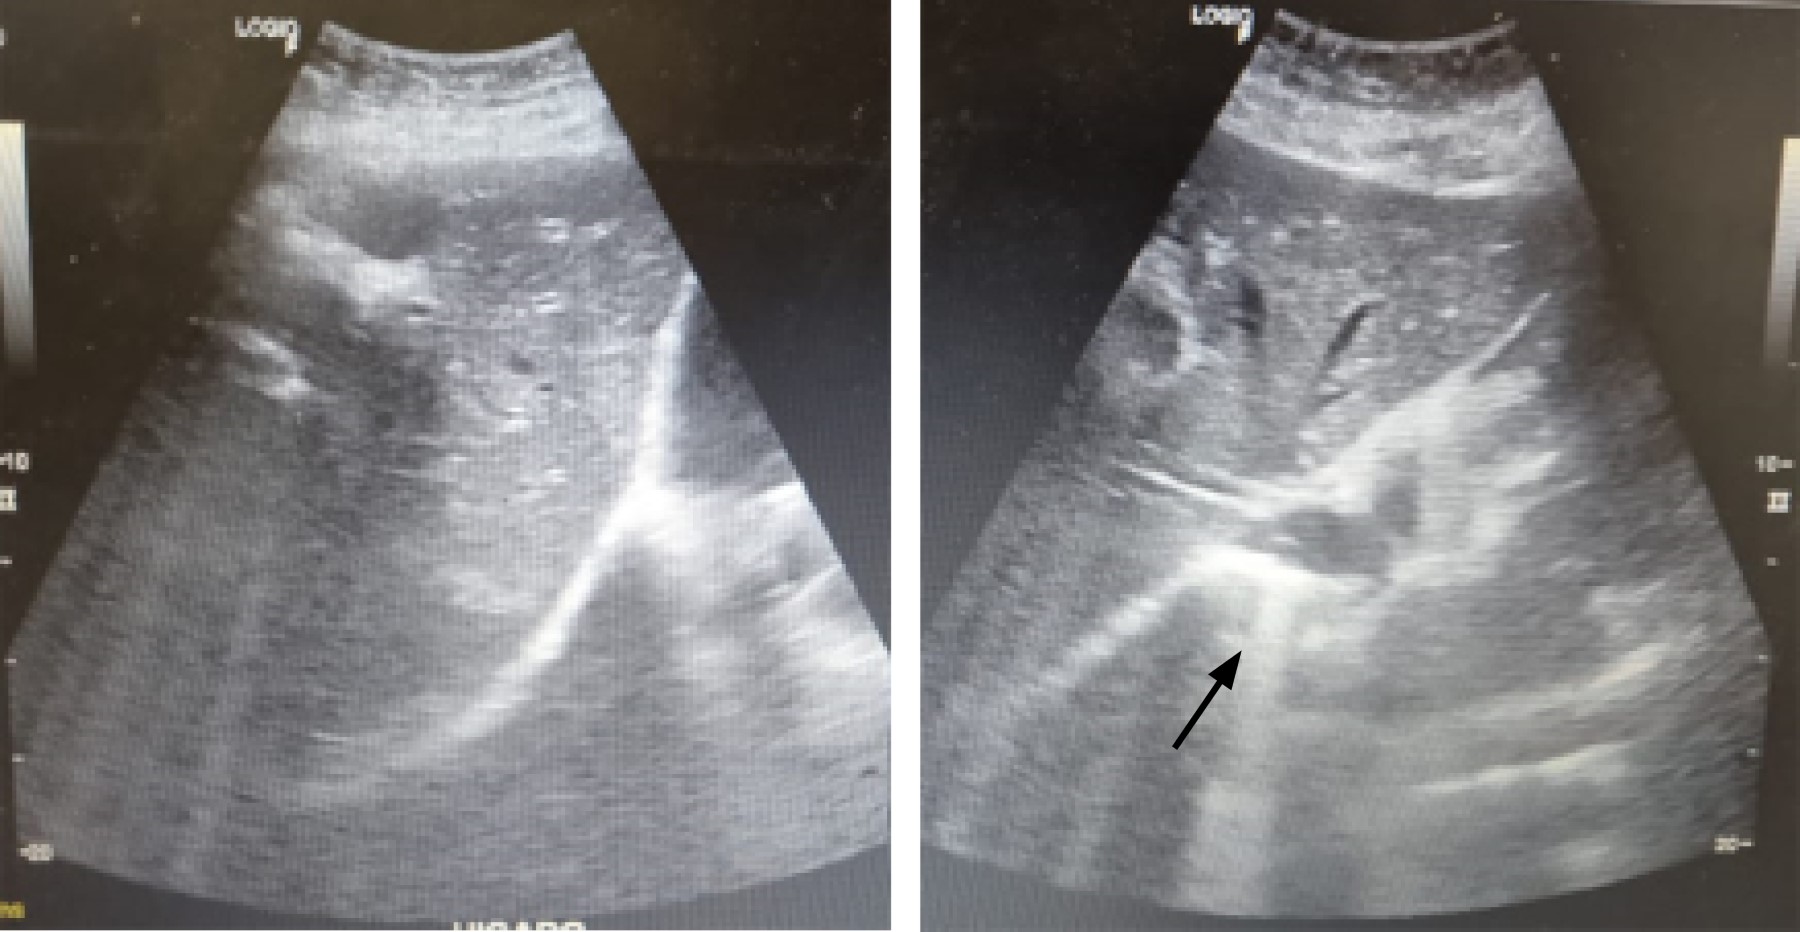

The patient was a 59-year-old female with a history of type 2 diabetes mellitus of long evolution. She came to the emergency department with colicky pain in the right hypochondrium after six months of evolution, intensity 6/10 on the visual analog scale, without irradiation, associated with the ingestion of cholecystokinetic foods, without mitigating factors. She denied fever, jaundice, choluria, or acholia. On physical examination, the Murphy sign was absent, with pain on deep palpation in the right hypochondrium, with no evidence of peritoneal irritation. She has the following laboratories: hemoglobin 12.9 g/dl, hematocrit 37%, leukocytes 9.4 × 103/µl, platelets 360 × 103/µl, glucose 178 mg/dl, creatinine 0.7 mg/dl, sodium 145 mEq/l, potassium 3.7 mEq/l, chlorine 105 mEq/l, total bilirubin 0.7 mg/dl, alkaline phosphatase 55 U/l. Ultrasound of the liver and biliary tract was performed, which revealed an increased echogenicity of the gallbladder throughout its extension, causing a wall-echo-shadow (WES) phenomenon and measuring 52.7 × 29.4 × 18.7 mm. The wall was non-evaluable; the common bile duct measured 5.8 mm, with no evidence of any litho inside (Figure 1). An abdominal tomographic scan showed a heterogeneous gallbladder with a volume of 13.2 cm3, with the presence of air density and a regular thickened wall with the presence of calcifications, a distended stomach, and the presence of a hyperdense image inside resembling a probable litho (Figure 2).

Figure 1